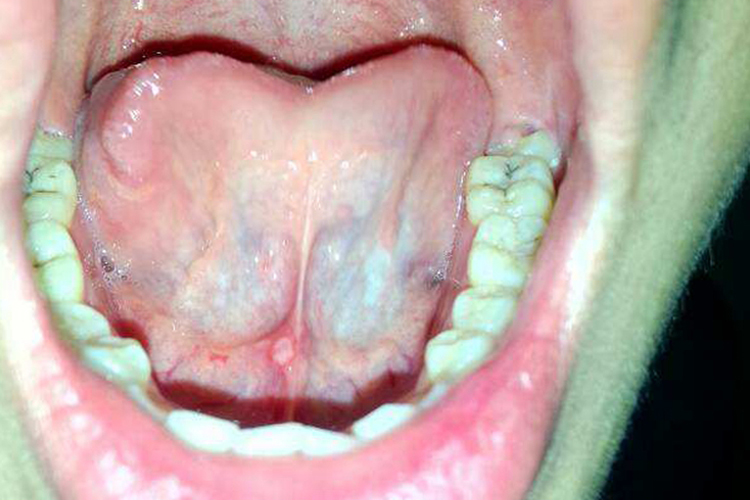

口底及舌下区是表皮样囊肿最常见的部位。皮损可呈白色肿块,生长缓慢、无痛,但在青春期可能生长稍快。扪诊肿块柔软,面团样感,无波动,和周围组织界限清楚。肿块一般位于中线,少数病例可偏向一侧。

涎石病

涎石病是指发生在涎腺腺体及其导管中的钙化性团块而引起的一系列病变,小的涎石一般不造成唾液腺导管阻塞,无症状。典型的导管结石为长圆形,呈枣核状,可表现为舌系带上白色疙瘩。